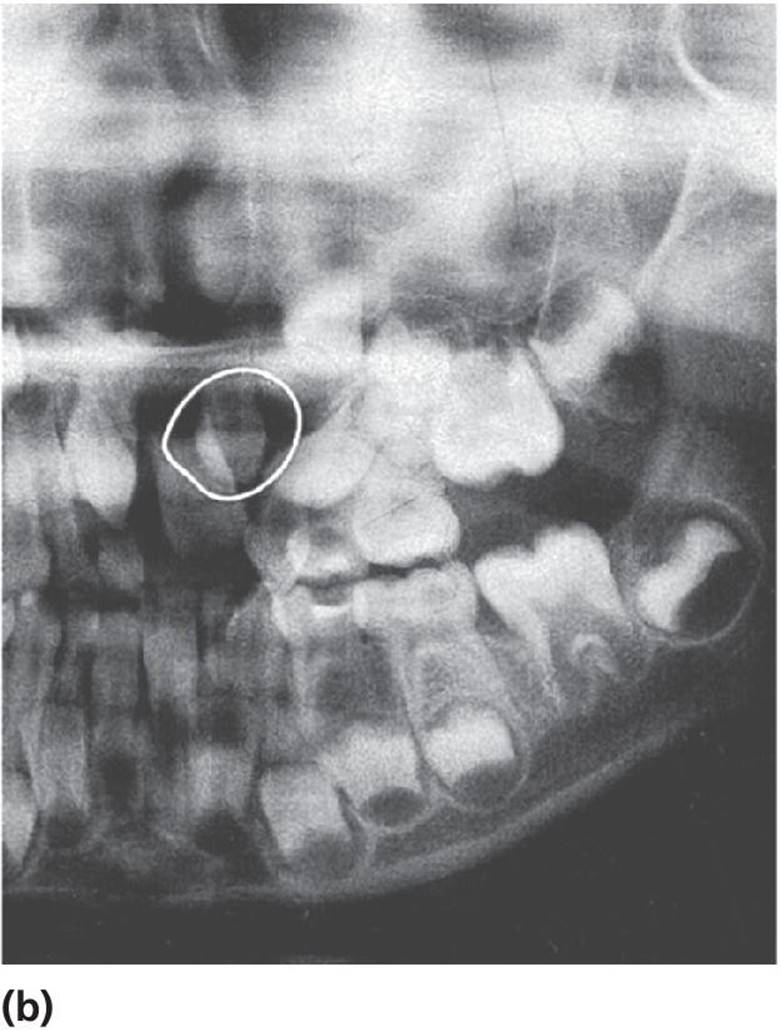

Cysts in the jaws, and especially large follicle cysts emerging from non‐erupted teeth, may displace teeth under development and disturb their eruption (Figure 15.29a–c). In children, it is important not to remove the cysts surgically as a first step procedure since this might damage a number of teeth and tooth germs. Instead, it is recommended in cases with large cysts that the cyst should be shrunk by use of rinsing with saline through an obturator introduced through the cyst wall (Figure 15.29d). In young individuals, the cyst will rapidly decrease and will be substituted by bone and often the dislocated teeth will spontaneously find their normal positions and eruption pathways.

Figure 15.29 (a) Extensive dentigerous (follicular) cyst in left maxilla emerging from a supernumerary tooth and displacing tooth germs and disturbing normal eruption in a 5‐year‐old girl. (b) Radiographic examination after 5 months revealed that the cyst had been reduced considerably and was now available for surgical removal without risk of disturbing the involved teeth. (c) After 4 months and surgical removal of supernumerary teeth and residual cyst tissues. (d) Obturator inserted to facilitate rinsing of the cyst. The obturator was removed after 6 weeks.